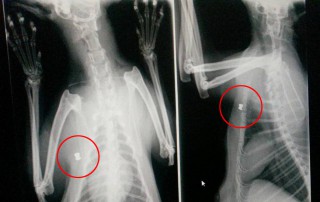

Richard macht sich Sorgen. Fuss kaputt, weil sie unters Pferd gekommen ist, ne Kugel in der Brust und acht Junge…Diese Katze hat kein gutes Leben.